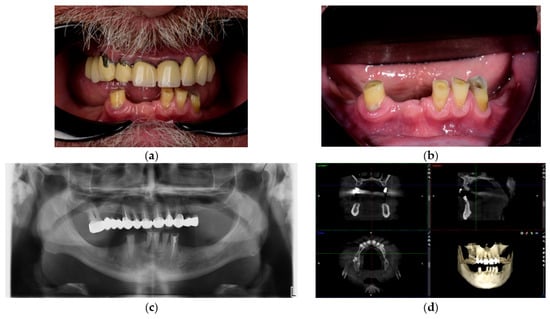

21 pages, 7578 KB

Article

Comparative Clinical Evaluation of Digital Versus Conventional Dental Impression Techniques in Implant-Supported Restorations

by Ioan-Achim Borșanu, Laura-Cristina Rusu, Sergiu-Manuel Antonie and Emanuel-Adrian Bratu

Background: This retrospective comparative clinical study aimed to evaluate the performance of digital versus conventional impression techniques in the fabrication of implant-supported prosthetic restorations. Materials and Methods: A total of 40 cases were included: 20 impressions obtained with conventional elastomeric materials (polyvinyl siloxane [...] Read more.

Background: This retrospective comparative clinical study aimed to evaluate the performance of digital versus conventional impression techniques in the fabrication of implant-supported prosthetic restorations. Materials and Methods: A total of 40 cases were included: 20 impressions obtained with conventional elastomeric materials (polyvinyl siloxane and polyether), and 20 impressions acquired digitally using two intraoral scanners (TRIOS 3 and Medit i700). All patients received partial fixed implant restorations and were documented across all stages of prosthetic treatment. Accuracy and passive fit were assessed using radiographic measurements and the Sheffield test. Linear distances (mm) at the implant–abutment interface, chairside time (min), and VAS scores (1–10) were analyzed. Clinical efficiency was evaluated based on procedural steps, chairside time, and adjustment frequency. Patient satisfaction was assessed through a structured 10-item Visual Analog Scale (VAS) questionnaire. Results: Results showed a lower misfit rate in the digital group (15%) compared to the conventional group (25%), with no final-stage misfits in digital cases. Digital workflows demonstrated shorter impression times, fewer procedural steps, and reduced the need for prosthetic adjustments. Patient satisfaction scores were significantly higher in the digital group across all VAS parameters (p < 0.001), particularly in comfort and esthetic satisfaction. Conclusions: These findings support the use of digital impressions as a clinically efficient and patient-preferred alternative to conventional methods for partial implant restorations. However, conventional impressions remain a viable option in settings where digital technology is not available. Further studies with larger sample sizes and long-term follow-up are recommended to assess outcomes in full-arch rehabilitation. Full article